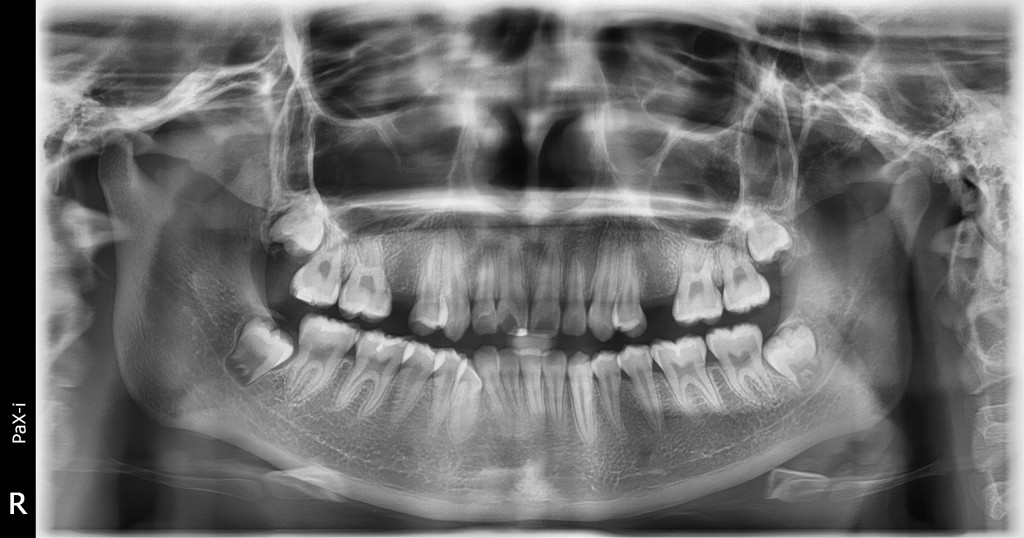

RADIOGRAFÍA

PANORÁMICA

• Muestra en una sola toma toda la estructura bucal.

• Planificación de tratamientos.

• Detección temprana de problemas

• Detección de problemas óseos.

• Es una toma rápida no invasiva.